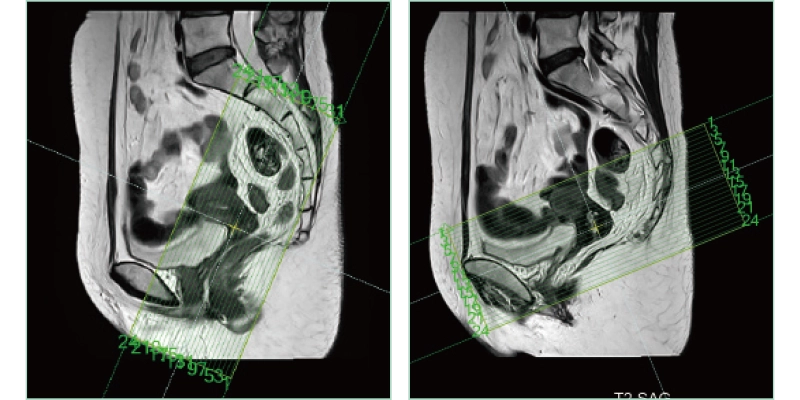

AutoPose FemalePelvis

The slice line setting support function, "AutoPose," automatically sets the slice lines as soon as the scanogram is scanned.

AutoPose Knee